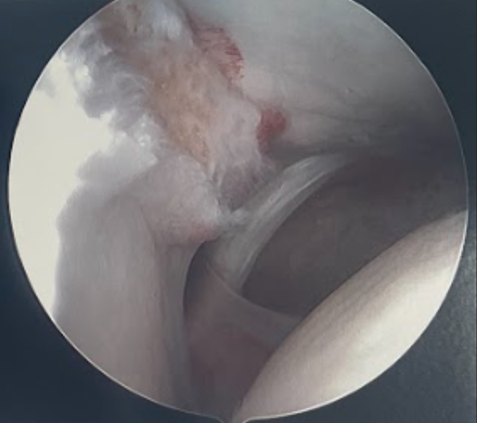

- talar dome and tibial plafond for chondral lesions

Talar dome